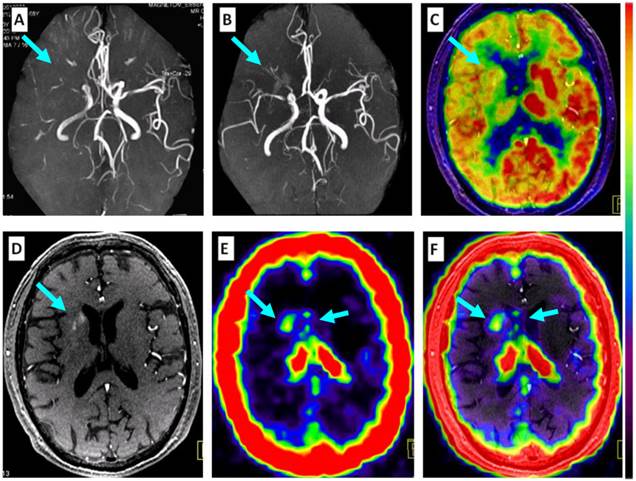

Figure 5

Comparison of 68Ga-PRGD2 PET with MRA, contrast-enhanced MRI, and 18F-FDG PET in evaluation of a 68-year-old man 2 weeks after a stroke event. Magnetic resonance angiography (MRA) on the day of the event showed obstruction of the right middle cerebral artery (A, arrow), which was still observed to be severely stenotic 2 weeks later (B, arrow). 18F-FDG PET showed diffuse low metabolism in the right hemisphere, mainly involving the frontal cortex and the basal ganglia region (C, arrow). Enhanced brain MRI showed a flaky subacute infarction area near the anterior horn of the right lateral ventricle (D, arrow). Multifocal lesions with 68Ga-PRGD2 uptake were found around the infarction region (E, F, arrows) with a pSUV of 0.57.

Figure 6

Comparison of a patient with a severe stroke attack and another patient with a minor event. Upper row: In a 43-year-old man at the 26th day after the event, the right frontal lobe with low density on CT (A, arrows) and significantly decreased 18F-FDG uptake (B, arrows) is found with diffuse multifocal 68Ga-PRGD2 uptake (C, arrows) with a pSUV of 0.72. Lower row: In a 37-year-old woman on the 24th day after the event, a relatively small region at the right basal ganglia shows decreased density on CT (D, arrow), low 18F-FDG uptake (E, arrow), and sparse spotted 68Ga-PRGD2 uptake around the lesion, with a pSUV of only 0.28 (F, arrow).